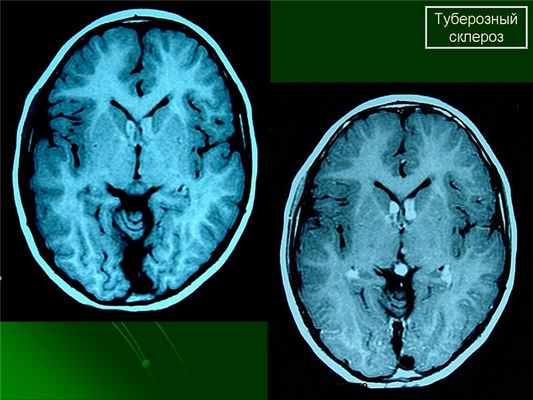

Субэпиндемальные узлы и корковые туберсы на МРТ

(Справа) КТ крестца, аксиальный срез: определяются склеротические образования. Гем не менее, также имеется несколько литических образований. Обе картины характерны для костных образований туберозного склероза и могут определяться при метастазах или при миеломе, но заболевание почек свидетельствует в пользу туберозного склероза. (Слева) МРТ, FLAIR, аксиальный срез: у этого же пациента определяются характерные субкортикальные бугры. При туберозном склерозе неврологические признаки являются наиболее распространенными, далее идут сим птомы поражения почек, а затем костные образования.

При подозрении на эту болезнь обязательно следует проводить МРТ головного мозга. При этом в головном мозге выявляются характерные МРТ-признаки туберозного склероза: корковые и подкорковые узлы (туберсы), субэпендимальные узелки (гамартомы), а также различные изменения белого вещества – очаговые и кистозные.

МРТ головного мозга при туберозном склерозе. Участки изменения МР-сигнала неправильной формы в коре и подкорковом белом веществе — так называемые корковые туберсы.